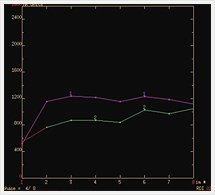

乳房

MRIは他のモダリティに比べて乳管内癌の検出に優れ、乳癌の治療に際して広がり診断や多発などの存在診断に有用です。

造影剤を急速静注しながら連続撮影するダイナミック撮像が特に有用で、得られた画像から腫瘍のダイナミックカーブを作成します。これによって腫瘍の進展範囲の把握や良性悪性の質的診断を行っています。